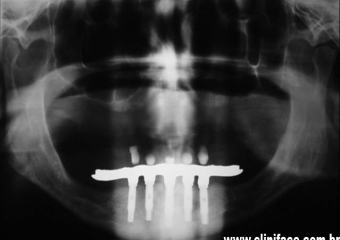

Raio X com implantes instalados